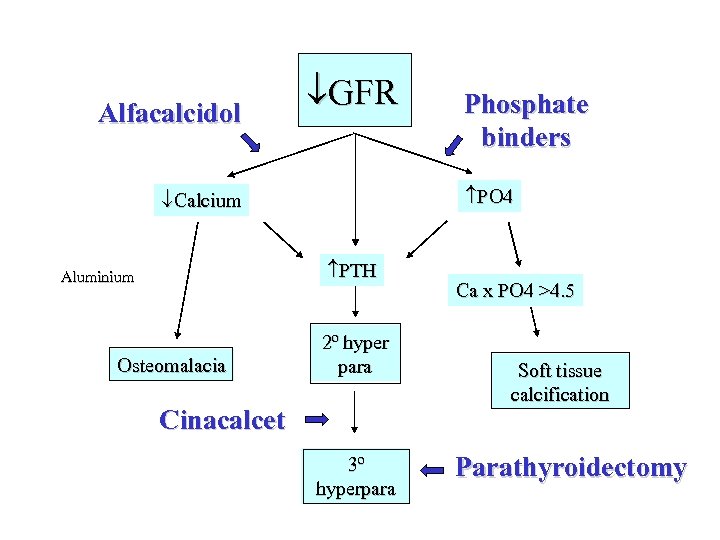

Hydroxylation Vitamin D GFR Calcium Aluminium Osteomalacia Phosphate retention PO 4 PTH 2º hyper para 3º hyperpara Ca x PO 4 >4. 5 Soft tissue calcification

Hydroxylation Vitamin D GFR Calcium Aluminium Osteomalacia Phosphate retention PO 4 PTH 2º hyper para 3º hyperpara Ca x PO 4 >4. 5 Soft tissue calcification

Clinical features • May be none • Soft tissue calcification - itch, red eye, calciphylaxis and (probably) increased risk CHD due to coronary calcification • 2 y hyperpara - high PO 4 with low Calcium, may cause bone pain, fractures • Osteomalacia - bone pain, rickets in childhood, proximal myopathy, fractures NB Osteitis fibrosa cystica is the term used to describe the appearance of bone in 2 y hyperpara. In severe cases, proliferation of osteoclasts results in cyst formation in bone called a “brown tumour” which is not premalignant

Clinical features • May be none • Soft tissue calcification - itch, red eye, calciphylaxis and (probably) increased risk CHD due to coronary calcification • 2 y hyperpara - high PO 4 with low Calcium, may cause bone pain, fractures • Osteomalacia - bone pain, rickets in childhood, proximal myopathy, fractures NB Osteitis fibrosa cystica is the term used to describe the appearance of bone in 2 y hyperpara. In severe cases, proliferation of osteoclasts results in cyst formation in bone called a “brown tumour” which is not premalignant

Treatment of renal bone disease • Anything that keeps PO 4 <1. 8 mmol/l! • - low PO 4 diet which means restricting dairy products • - calcium carbonate (calcichew) or acetate (phosex) before food • - aluminium hydroxide (alucaps) before food • - sevelamer (renagel - non Ca non Al polymer) before food • - lanthanum (fosrenol) after food • - dialysis - but not very efficient at removing PO 4

Treatment of renal bone disease • Anything that keeps PO 4 <1. 8 mmol/l! • - low PO 4 diet which means restricting dairy products • - calcium carbonate (calcichew) or acetate (phosex) before food • - aluminium hydroxide (alucaps) before food • - sevelamer (renagel - non Ca non Al polymer) before food • - lanthanum (fosrenol) after food • - dialysis - but not very efficient at removing PO 4

Treatment of renal bone disease • Alfacalcidol or calcitriol (1: 25 DHCC) to keep calcium normal and PTH 2 -4 times ULN after controlling PO 4 • Cinacalcet (Mimpara) for severe 2 y HPT • Parathyroidectomy for 3 y HPT, uncontrollable itch with high Ca-PO 4 product and calciphylaxis (skin necrosis) NB Hypercalcaemia assoc with renal bone disease does not respond to oral steroids and renal osteomalacia does not respond to 25 OHD

Treatment of renal bone disease • Alfacalcidol or calcitriol (1: 25 DHCC) to keep calcium normal and PTH 2 -4 times ULN after controlling PO 4 • Cinacalcet (Mimpara) for severe 2 y HPT • Parathyroidectomy for 3 y HPT, uncontrollable itch with high Ca-PO 4 product and calciphylaxis (skin necrosis) NB Hypercalcaemia assoc with renal bone disease does not respond to oral steroids and renal osteomalacia does not respond to 25 OHD

Alfacalcidol GFR PO 4 Calcium PTH Aluminium Osteomalacia Phosphate binders 2º hyper para Cinacalcet 3º hyperpara Ca x PO 4 >4. 5 Soft tissue calcification Parathyroidectomy

Alfacalcidol GFR PO 4 Calcium PTH Aluminium Osteomalacia Phosphate binders 2º hyper para Cinacalcet 3º hyperpara Ca x PO 4 >4. 5 Soft tissue calcification Parathyroidectomy